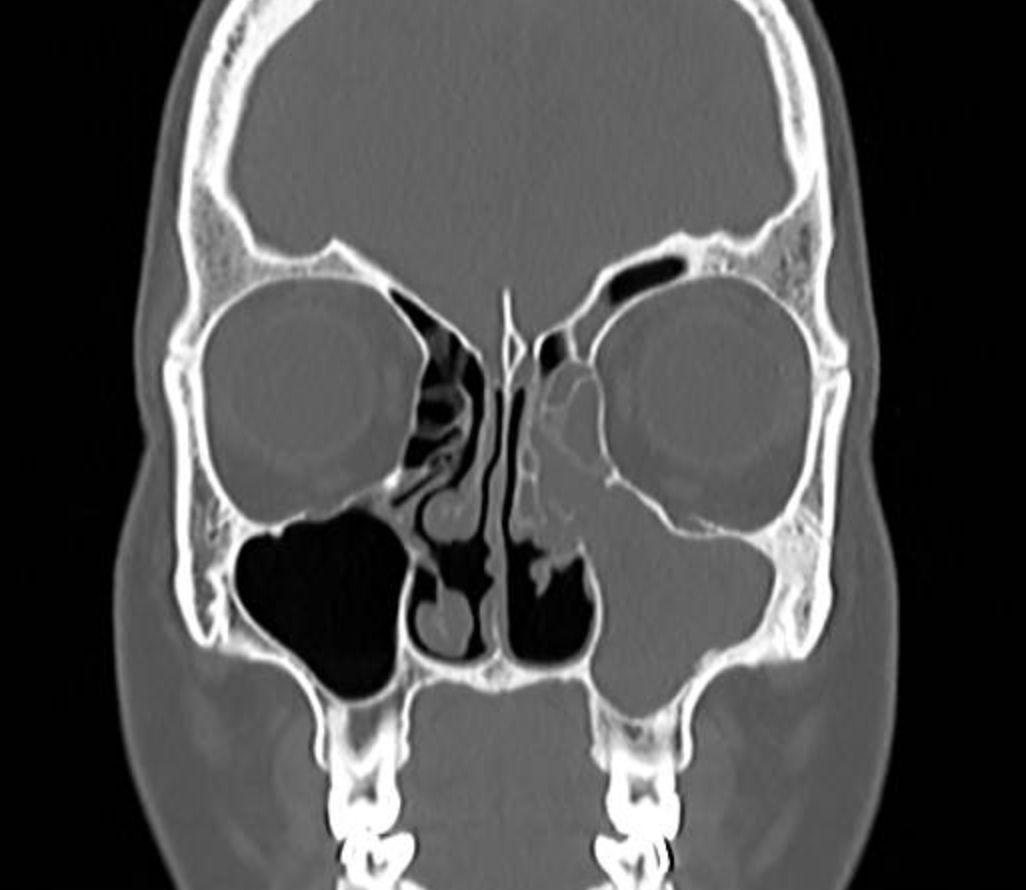

Laudo de tomografia de face: o que significa e quando pode indicar cirurgia

Entenda os termos mais comuns do laudo de tomografia de face: o que significam, quando podem indicar cirurgia e quando são apenas observação.